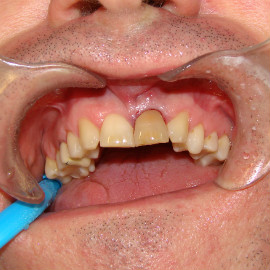

Bezzębie całkowite górne. Początkowo wykonane na mieście mosty całoceramiczne wydawały sie sukcesem, ale po roku pojawiły sie obrzęki i krwawienie z dziąseł. Pacjentka zgłosiła się do leczenia. Usunięto wszystkie zęby w szczęce. Sterowana regeneracja tkanek kości wyrostka, modelowanie kształtu i objętości tkanek miękkich, mosty porcelanowe przykręcane do implantów. Zadowalający wynik anatomiczny i estetyczny.